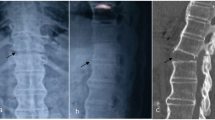

This is a case report describing the injury sustained by a 36-year-old man injured in a motorcycle crash who sustained a fracture–dislocation of L2 upon L3, associated with a split in the lamina of L3. His neurologic lesion was T12 ASIA B: with a motor score of 52 but with preservation of sensory function (sensory score 96) in most parts of his lower extremities. He also suffered a lower extremity fracture. Imaging of the spine is presented showing a multiplanar fracture associated with translation and with a defect in the lamina that may be seen in certain AO type B or type C fractures, that may entrap the lumbar spinal nerve roots. Discussants of this case comment on the classification and clinical significance of this fracture pattern, and present their operative approaches, both for management of this particular fracture pattern and for any associated dural tear. The issues of steroid use and the place of rehabilitation are also discussed.